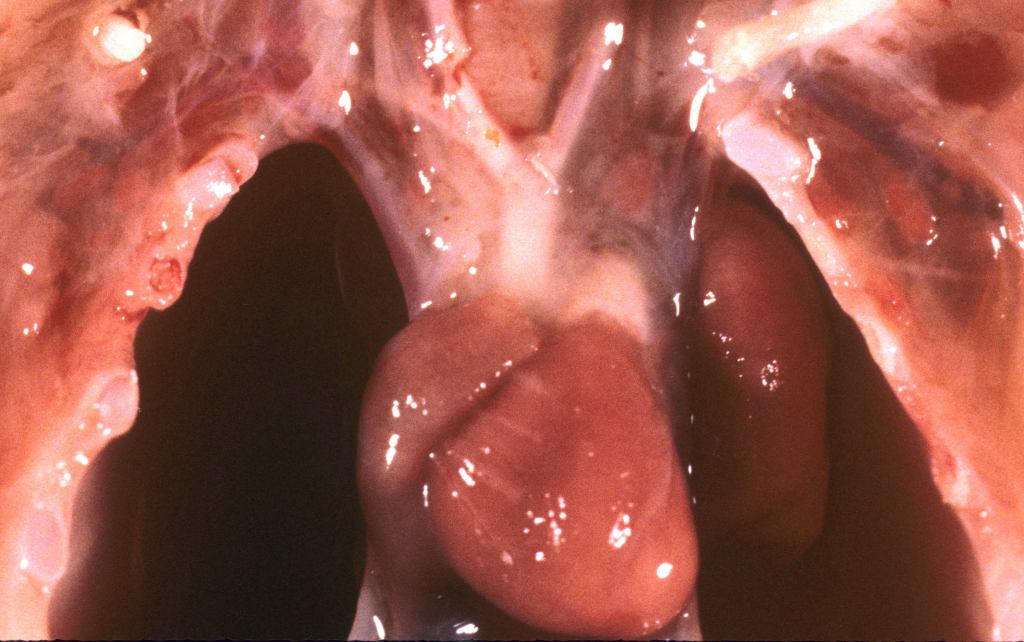

Pulmonary hypoplasia: Pulmonary hypoplasia may be apparent on opening the chest because the small lungs are obscured by the heart (Fig 1a,b).